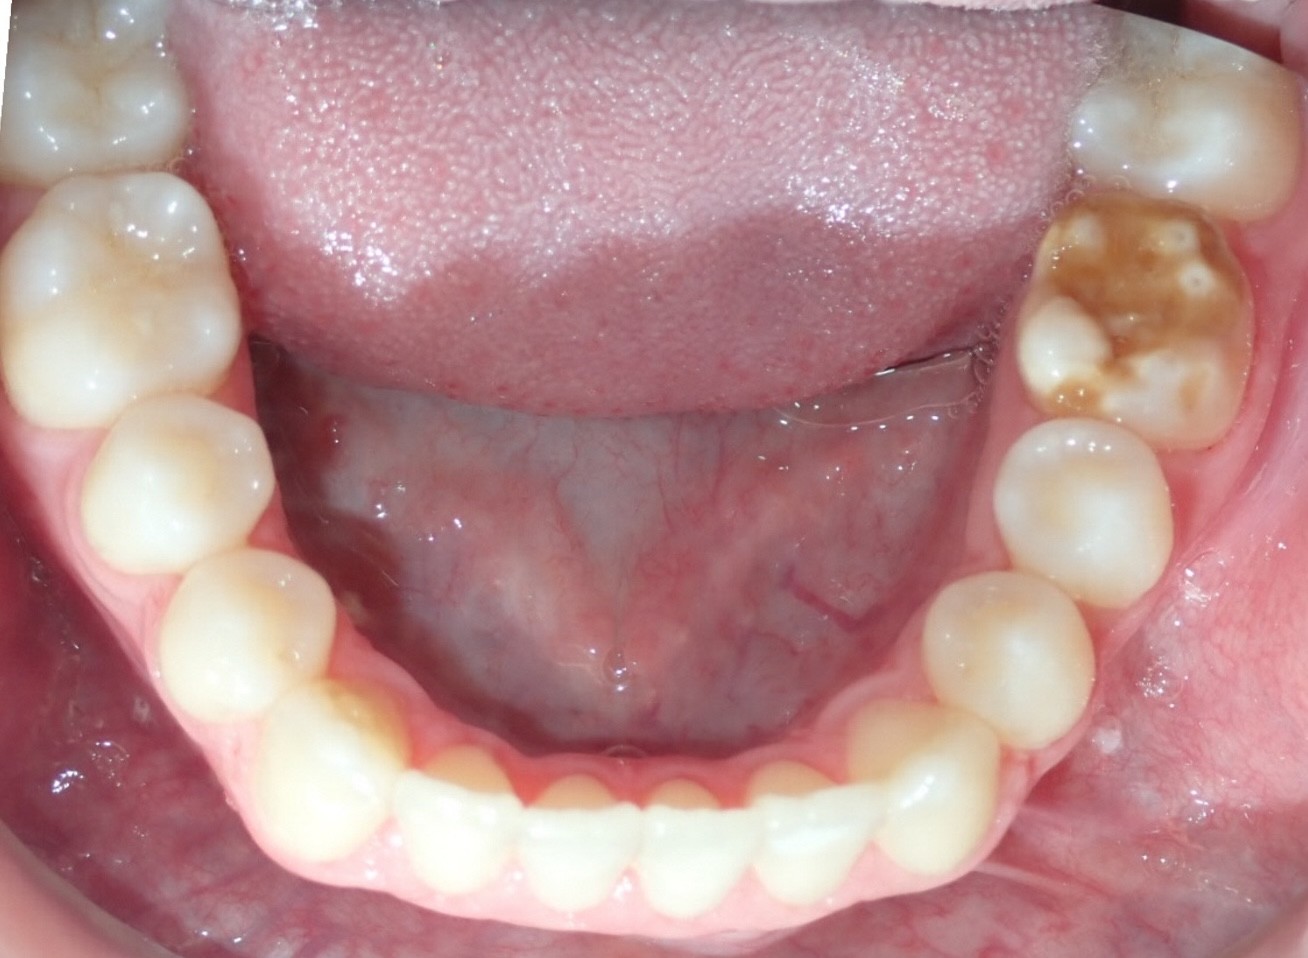

Initial treatment

INTRAORAL